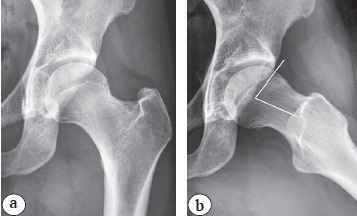

Учитывая, что чаще всего cam-деформация головки/шейки бедренной кости локализуется в промежутке 11:45–2:45 условного циферблата для правого ТБС и 9:15–12:15 условного циферблата для левого ТБС, необходимо оценить сферичность передне-верхнего отдела головки/шейки бедренной кости [52, 53], даже если на снимке таза в прямой проекции нет данных о нарушении сферичности головки (рис. 5 а). С этой целью выполняются рентгенограммы по Dunn 45° с наружной ротацией бедра на 40° (рис. 5 b) и измеряется угол сферичности головки бедренной кости.

Рис. 5. Деформация передне-верхнего отдела головки/шейки бедренной кости:

a — рентгенограмма левого ТБС без признаков cam-деформации;

b — рентгенограмма левого ТБС в положении по Dunn 45° с ротацией 40°

Fig. 5. Deformation of the anterior superior part of femoral head/neck:

a — left hip X-ray without signs of cam-deformity;

b — left hip X-ray in 45° Dunn position with rotation 40°

Выполнение cтандартной укладки по Dunn 45° подразумевает сгибание в бедре под углом 45°, отведение на 20° и нейтральное положение стопы [54, 55, 56]. Однако в литературе зачастую выполнение укладки по Dunn 45° в классическом варианте заменяется на выполнение этой укладки с ротацией 40°. При сгибании в ТБС на 45° и наружной ротации бедра на 40° выявление деформации улучшается [57]. Иногда возникает ситуация, когда при измерении угла a мы получаем значение меньше 50–55°, однако визуально можно определить снижение сферичности головки бедренной кости (рис. 6 а). В этой ситуации будет полезно измерение офсетного коэффициента (отношение расстояния между параллельными линиями оси шейки, которые проводятся по краю шейки и краю головки бедренной кости к диаметру головки), величина которого в норме должна быть более 0,17 (рис. 6 b) [56]. Значение менее 0,17 говорит о наличии cam-деформации.